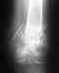

Чрезвертельный перелом левого бедра, в результате ДТП. Женщина 56 лет, ДТП. Чрезвертельный перелом. Было выполнено: скелетное вытяжение- 1 месяц, остеосинтез Г- образной пластиной (Россия), через 4 месяца второй остеосинтез, через 4 месяца вылез винт, выполнена операция- удален один винт, аллопластика. Наложена кокситная повязка. Через 2,5 месяца: щель перелома прослеживается на всем протяжении, склероз по краям отломков. Болей нет. Посоветуйте, что делать дальше, к кому и куда обратиться за помощью. Проживаю в СПб.

Сейчас конструкция несостоятельная. Надо в любом случае ее удалять и заменять на другую, чтобы обеспечить немедленную возможность ходьбы с нагрузкой без риска смещения. Времени на лечение уже ушло в несколько раз больше обычного.

У нас в отделении сейчас делается довольно много операций по такого рода поводам. Предпочли бы сделать остеосинтез стержнем. Есть модификации, исключающие миграцию, подобную случившейся. Делать какие-то пластики и вообще широко обнажать кость не видно необходимости. Возможно, будет целесообразно увеличить шеечно-диафизарный угол.

Технических вариантов несколько, для выбора конкретного варианта надо посмотреть и очно, и предшествующие снимки, и сделать снимок таза с обоими тазобедренными суставами.